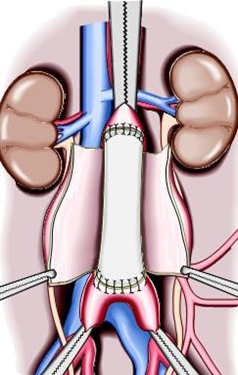

+ Phẫu thuật mở thay đoạn động mạch chủ bụng: Khi khối phình ≥ 5cm hoặc khi phình có nguy cơ vỡ bác sỹ sẽ chỉ định phẩu thuật.

+ Can thiệp nội mạch đặt ống ghép nội mạch ( Stent Graf )

Gọi là “nội mạch” là vì điều trị được thực hiện bên trong lòng động mạch bằng cách dùng những ống nhỏ dài và mỏng được gọi là catheters để luồn qua những động mạch. Phương pháp này ít xâm lấn hơn vì bác sĩ phẫu thuật thường sẽ chỉ cần thực hiện những đường rạch nhỏ ở vùng đùi để luồn những catheters vào đó. Đưa ống thông có gắn stent graft qua động mạch đùi đến vị trí phình để tạo đường dẫn máu mới, giảm áp lực lên túi phình. Thường áp dụng cho túi phình lớn hoặc bệnh nhân có bệnh nền. Đặt ốngghép nội mạch giúp giảm số ngày nằm viện, giảm các biến chứng, giảm tử vong, đặc biệt tử vong sớm; tuy nhiên giá thành của phương pháp điều trị này vẫn còn cao.